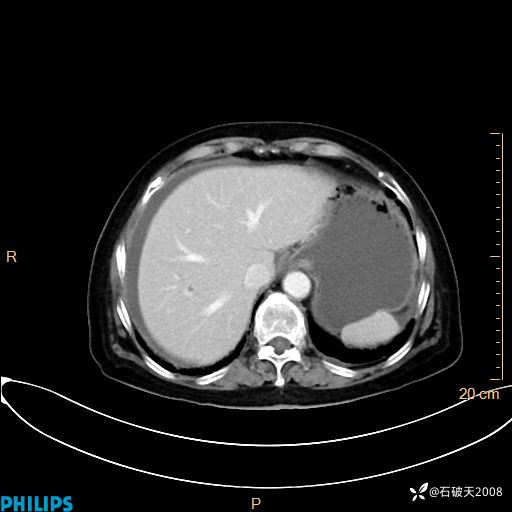

动脉期